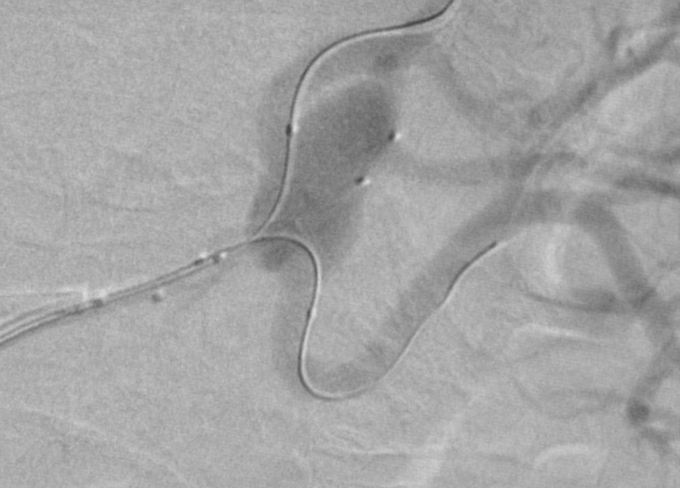

Treatment of complex aneurysms: Treatment of complex intracranial aneurysms often involves balloon-remodeling, stent-assisted coiling, or flow diverters. These methods can also be used for non-neurovascular procedures, specifically in treatment of visceral aneurysms. Renal artery aneurysms are most frequently located in the renal hilum, where the main renal artery diverts into its ventral and dorsal branch. Preservation of all renal artery branches may request advanced techniques as mentioned above (1); Fig 1,2.

Fig. 2: Double balloon assisted embolisation in dual catheter technique was applied

Fig. 3: Successful exclusion of the aneurysm with preservation of both renal artery branches